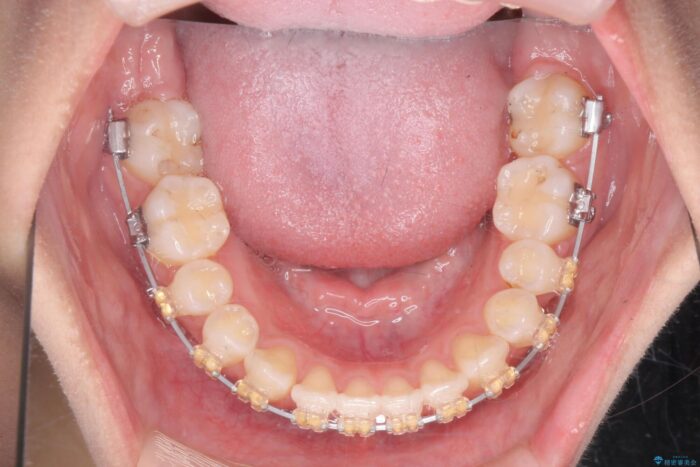

噛まない前歯と捻じれてしまった歯を改善したいと、矯正治療を希望された患者様です。

マルチブラケットを用いた非抜歯のワイヤー矯正で噛み合わせと歯並びを改善していきます。